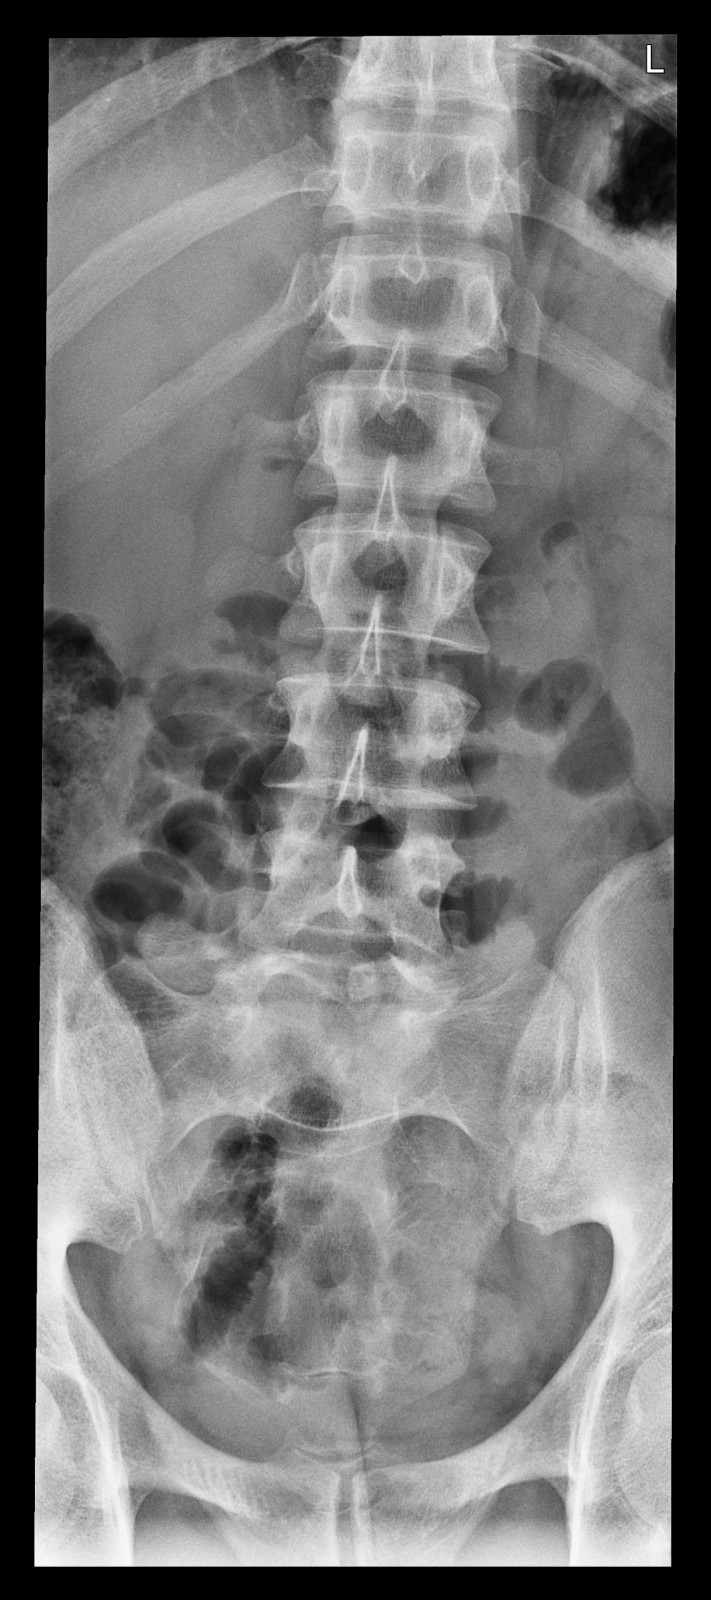

Röntgenfall des Monats Juni 2017 mit Auflösung

34 jähriger Patient mit exazerbierter Lumbago. Beruf: Plattenleger

ap

Bild vergrössern

Link zur Auflösung mit ausführlichem Befund:

https://www.radiologie24.ch/radiologie-mediathek/roentgenfall_des_monats